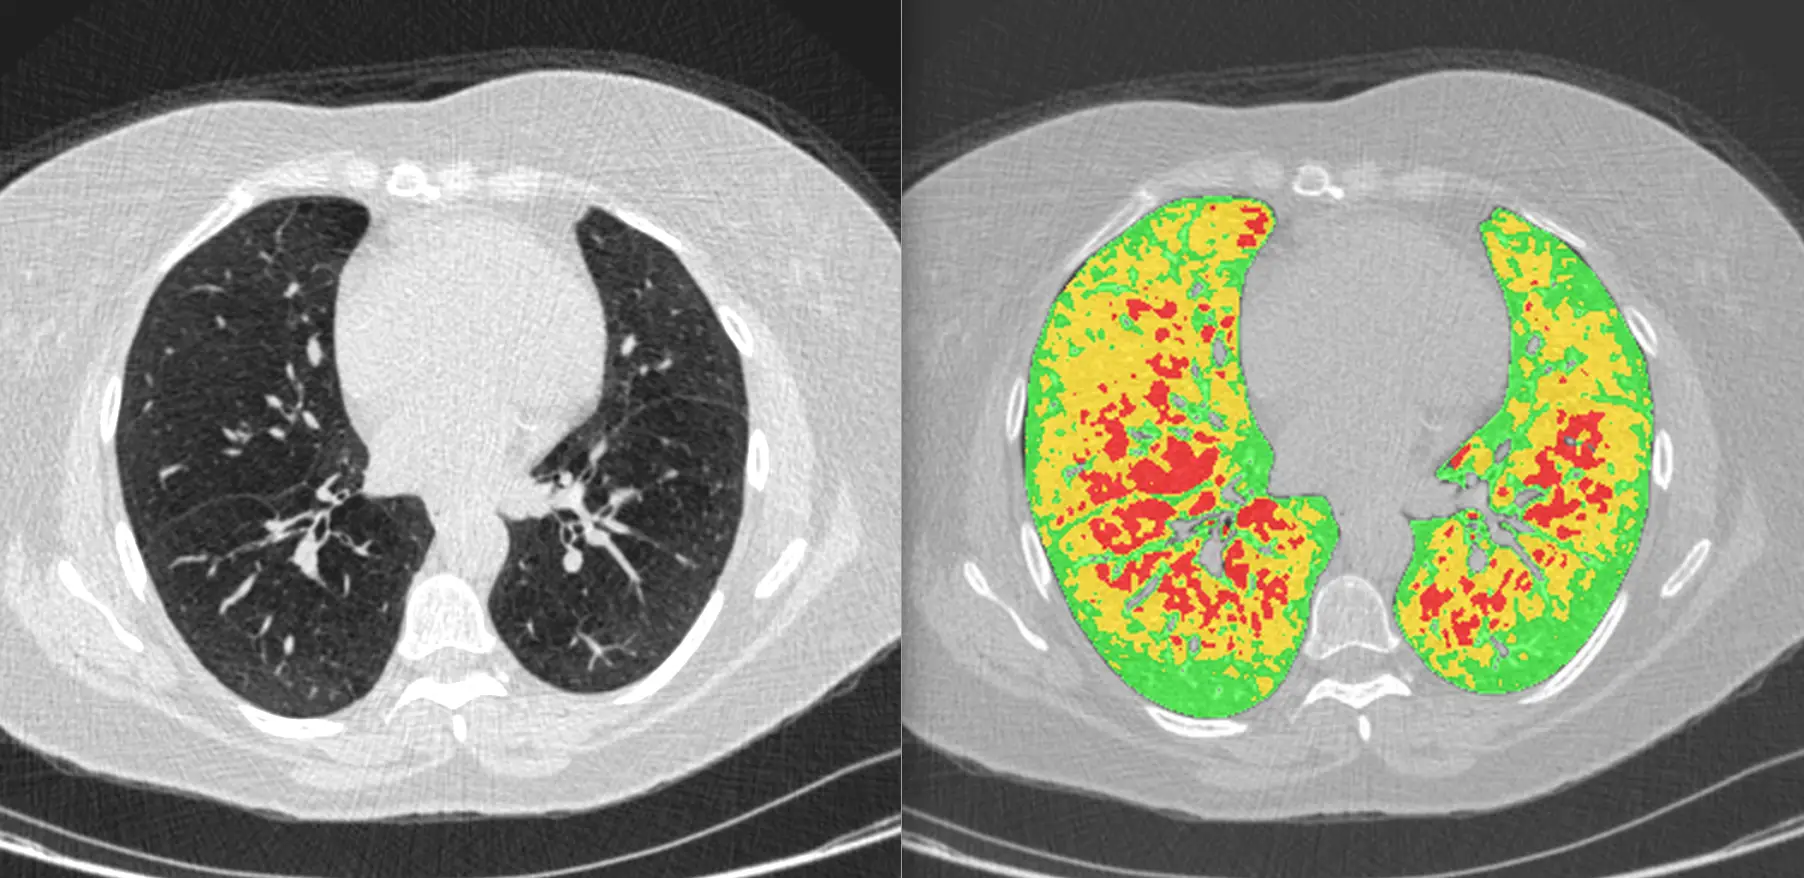

Our subspecialist chest radiology experts use cutting-edge Artificial Intelligence (AI) software to interpret your low-dose CT chest scan and provide a detailed lung health assessment. Our service is designed both for patients with symptoms as well as those with identified risk factors for lung disease, including lung cancer. H&L chest experts provide a detailed lung health report within 2 days.

A low dose CT scan with cutting edge AI enables detailed measurement of emphysema and the early diagnosis of lung fibrosis, including long COVID lung scarring.

Lung cancer assessment

H&L’s award-winning expertise in the detection of lung nodules on CT scans is specifically tailored to provide a diagnosis of lung cancer at its earliest, curable stage.